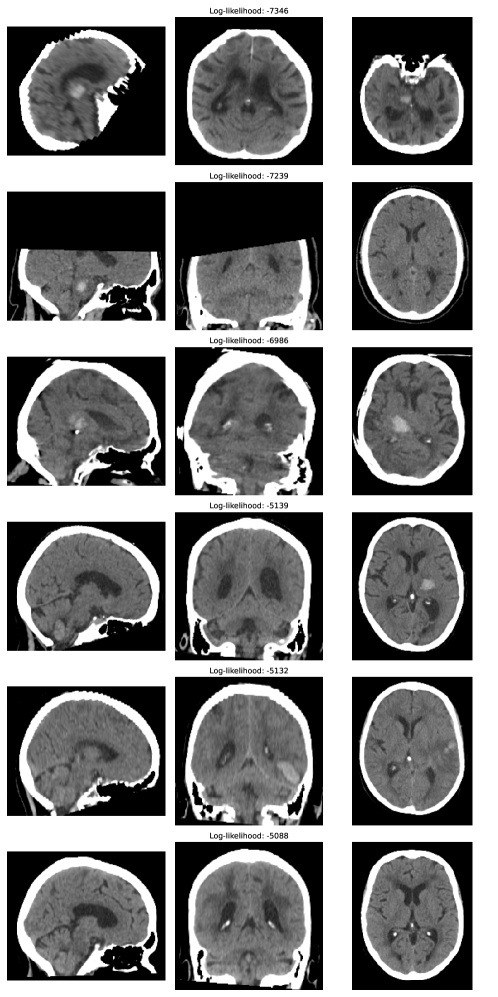

We examined the ability of transformers to filter out OOD inputs based on the whole-image log-likelihood. \figurereffig:likelihood_coarse_classes shows the distribution of log-likelihood values for far-OOD, near-OOD and in-distribution classes (plots showing each sub-class can be found in \figurereffig:likelihood_fine_classes). \tablereftab:likelihood_auc show the ability of the log-likelihood to distinguish OOD classes from normal head CT data. Performance is perfect for the far-OOD case. In the case of near-OOD data, classes on which the segmentation uncertainty performed poorly are distinguished well: images with adapted backgrounds, skull-stripping, and global intensity scaling are all distinguished with an AUC=1. Subtler corruptions, namely noise with and L-R flips, are not distinguished well. These are classes for which the segmentation network uncertainty measures perform well, suggesting these corruptions are more in-distribution and explaining why they have been assigned likelihoods more similar to the normal head CT data. This result also suggests transformers and segmentation networks with uncertainty may be used in tandem, with highly OOD images being filtered out by the transformer and the segmentation network providing meaningful uncertainty estimates on images that are only slightly OOD. \figurereffig:cromis_outliers shows some qualitative results on real data: the CROMIS volumes with the lowest and highest log-likelihood values as assigned by the transformer. \figurereffig:mse_plots shows that reconstruction MSE alone is unable to separate out in-distribution and OOD data, indicating the transformer component is essential for OOD detection.

fig:cromis_outliers